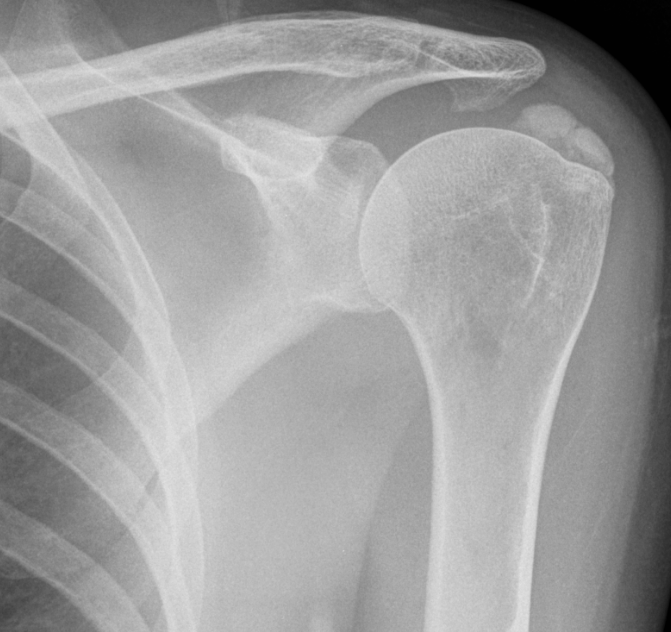

Calcific tendinopathy of supraspinatus